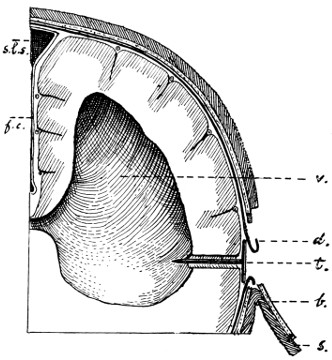

26. The author’s operation for Hydrocephalus internus 64

27. The conversion of Hydrocephalus internus into cephalocele 65